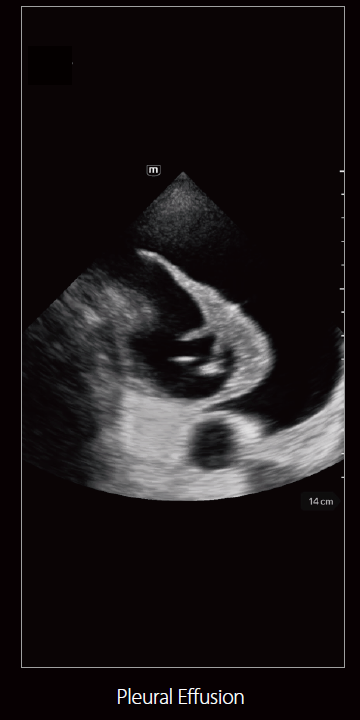

صور متعلقة